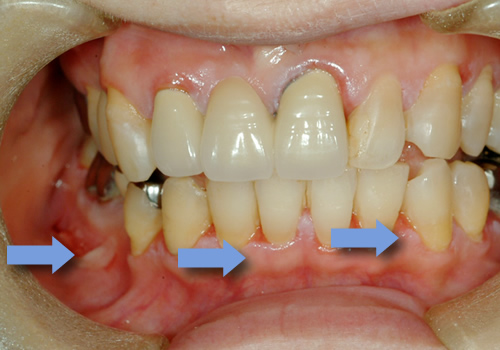

口腔扁平苔癬

口腔扁平苔癬は、罹患率が0.5〜3%で女性に多いと言われています。白色の網目状、レース状を呈する、ガーゼなどでぬぐい取れない病変で、赤色部分が混在する場合もあります。典型的なものは肉眼所見でも診断できる場合があります。

びらんや潰瘍を伴う場合は、疼痛も自覚します。WHO(世界保健機関)では、前がん状態とし取り扱われており、約2〜3%程度悪性化するとの報告もあります。